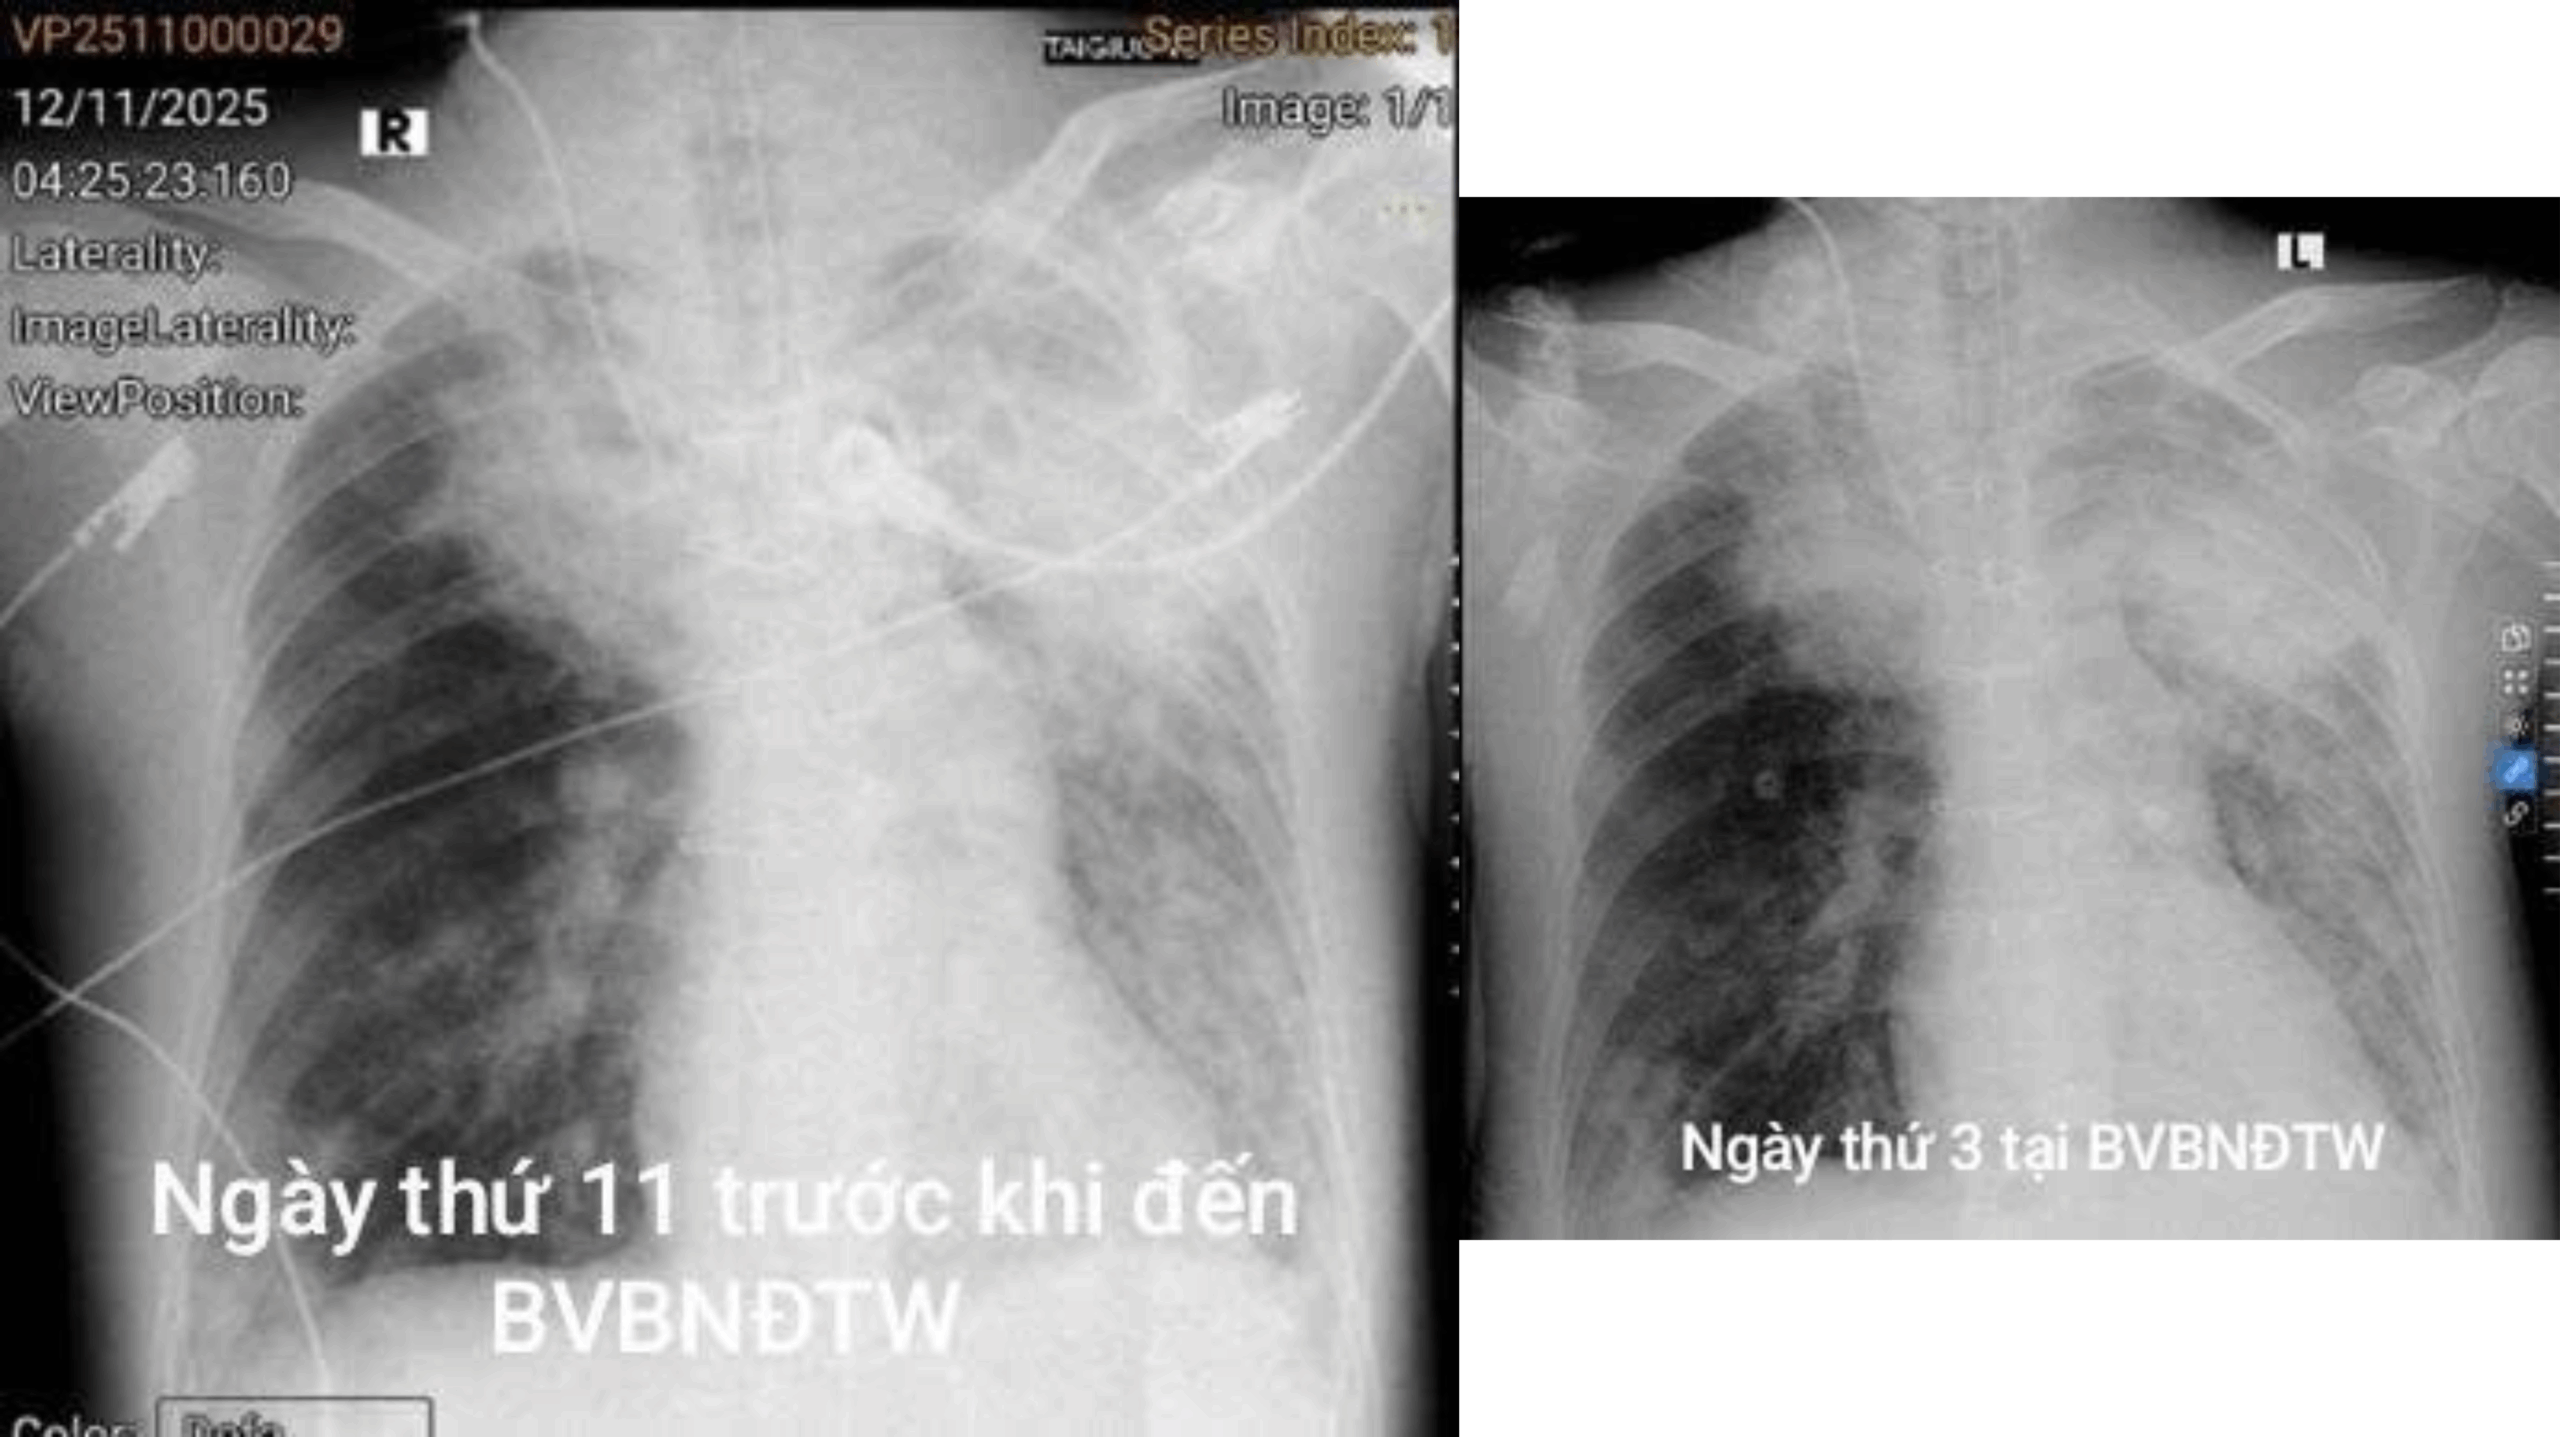

Ngày 1/11, anh được đưa vào bệnh viện chuyên khoa phổi và được chẩn đoán viêm phổi do cúm A kèm suy hô hấp. Tình trạng diễn tiến nhanh, bệnh nhân phải đặt nội khí quản thở máy, chức năng thận suy giảm và phổi tổn thương nặng dù đã dùng kháng sinh bao phủ. Sau 11 ngày điều trị nhưng không cải thiện, bệnh nhân vẫn sốt kéo dài. Kết quả nuôi cấy phát hiện nhiễm nấm Aspergillus, anh được chuyển tới Bệnh viện Bệnh Nhiệt đới Trung ương.

Tại Trung tâm Hồi sức tích cực, bác sĩ Hồng Kỳ cho biết bệnh nhân nhập viện trong tình trạng rất nặng: an thần, giãn cơ, thở máy, phải dùng thuốc vận mạch, cơ thể phù to, bụng chướng, dịch dạ dày xanh, nước tiểu vàng sậm; vùng cổ bàn chân trái bầm tím; loét lưng và loét cùng cụt độ 3; huyết áp tụt, phải duy trì noradrenalin. Khi soi phế quản và phát hiện giả mạc bám chắc tại nhánh phế quản phân thùy thùy trên trái, dễ chảy máu. Bệnh nhân được chẩn đoán nhiễm nấm Aspergillus xâm lấn phổi trên nền viêm phổi cúm A nặng, suy hô hấp, suy thận cấp, suy tim và sung huyết. Bệnh nhân được lọc máu liên tục và điều trị thuốc kháng nấm. Tuy nhiên, việc điều trị gặp nhiều khó khăn do bệnh nhân suy thận và có bệnh lý tim mạch, khiến khả năng hấp thu thuốc giảm, việc phối hợp điều trị phức tạp hơn.